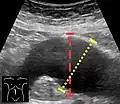

Aortic measurement on abdominal ultrasonography in the axial plane between the outer margins of the aortic wall[39] -

Ultrasonography in the sagittal plane, showing axial plane measure (dashed red line), as well as maximal diameter (dotted yellow line), which is preferred -